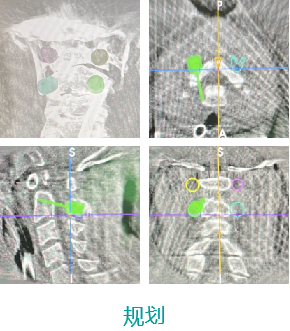

天玑II 辅助颈椎椎弓根螺钉内牢靠术